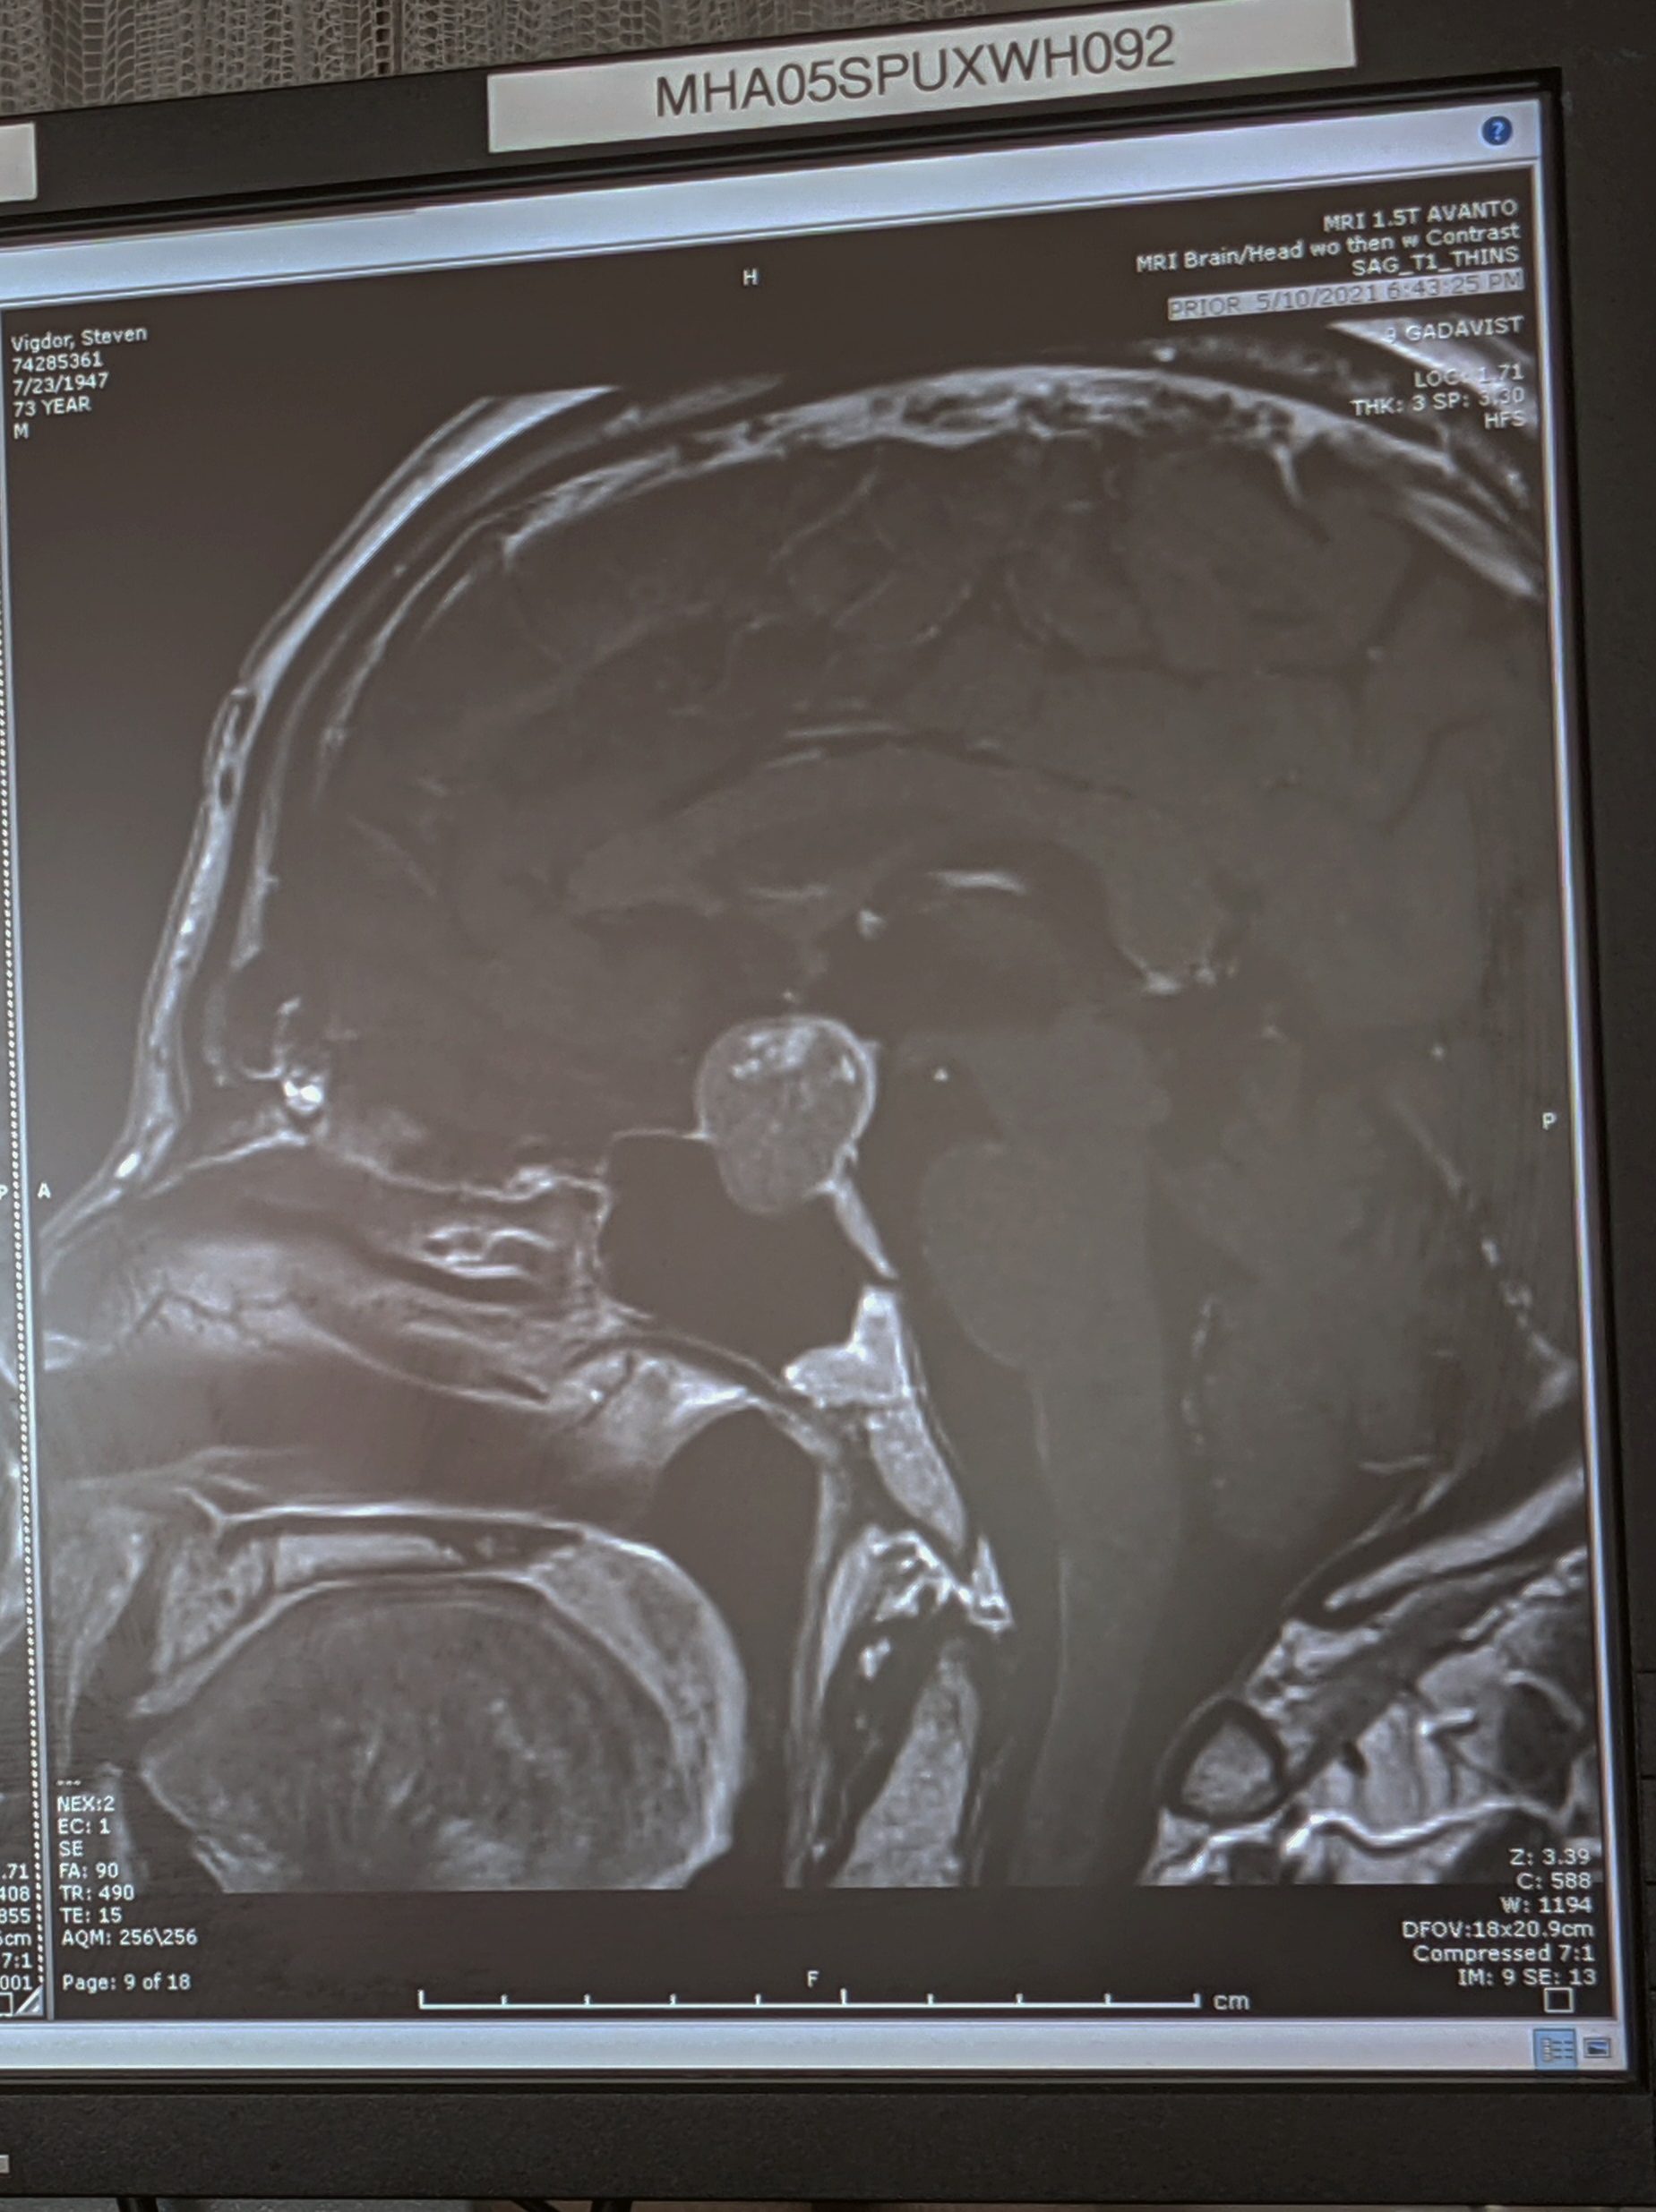

“If you have to have a brain tumor, yours is the one to have.” That’s what Dr. Jesse Savage told me shortly before he performed my neurosurgery. He showed me one of the MRI images of my tumor (see Fig. 8) and explained that it was exerting significant pressure on both the optic nerves and the pituitary gland. Much later, weeks after the surgery, I asked him what the normal diameter of the Sella is, and he told me it is “dime-sized.” My tumor was considerably larger than this and could fit in as it grew by not only squashing the pituitary, but also pushing out the walls of the Sella cavity.

Dr. Savage speculated that the lighter dots near the top of the tumor in Fig. 8 might indicate that the tumor itself had begun internal hemorrhaging. If so, that would make the extraction easier because the tumor matter would be squishy. It might also explain the sudden onset of my symptoms, because hemorrhaging tumors enlarge rapidly, leading to a condition called pituitary apoplexy.